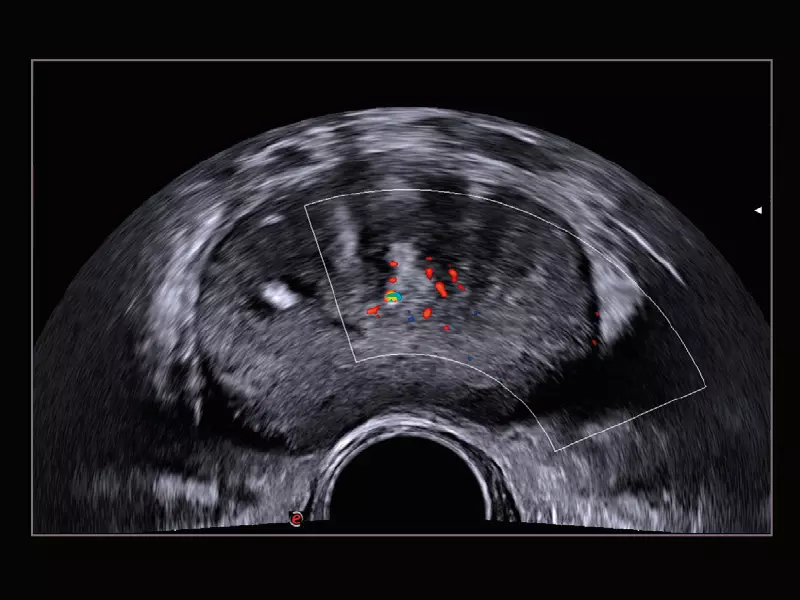

MyLab™9 Platform - Prostate contrast enhanced imaging (CnTI™)

MyLab™9 Platform - Prostate contrast enhanced imaging (CnTI™)